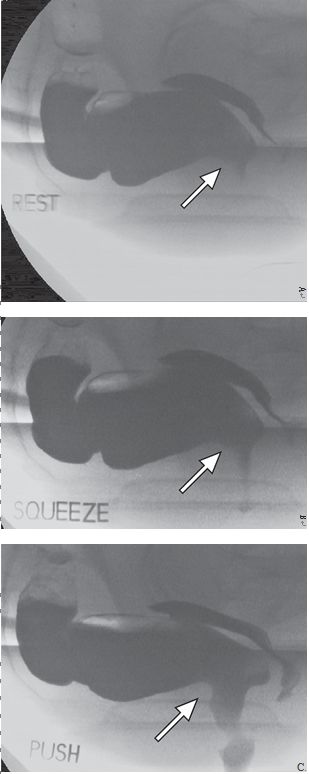

正常情况下肛直角在90°~110°。当排便开始时,肛直角会变钝,肛管变直。但有些患者会出现耻骨直肠肌悬带反常收缩,盆底松弛失败,引起排便梗阻,这种现象称为盆底失弛缓或者盆底痉挛(图1)。生物反馈技术治疗对一些患者有效。

图1 耻骨直肠肌悬带松弛功能受损,致盆底痉挛,阻碍排便。静息状态(A)、提肛状态(B)和力排状态(C)的排便造影图显示肛直角(箭)的变化,在提肛时应角度变小,力排时应角度变大。力排时耻骨直肠肌的压迹明显(C,箭),提示反常收缩